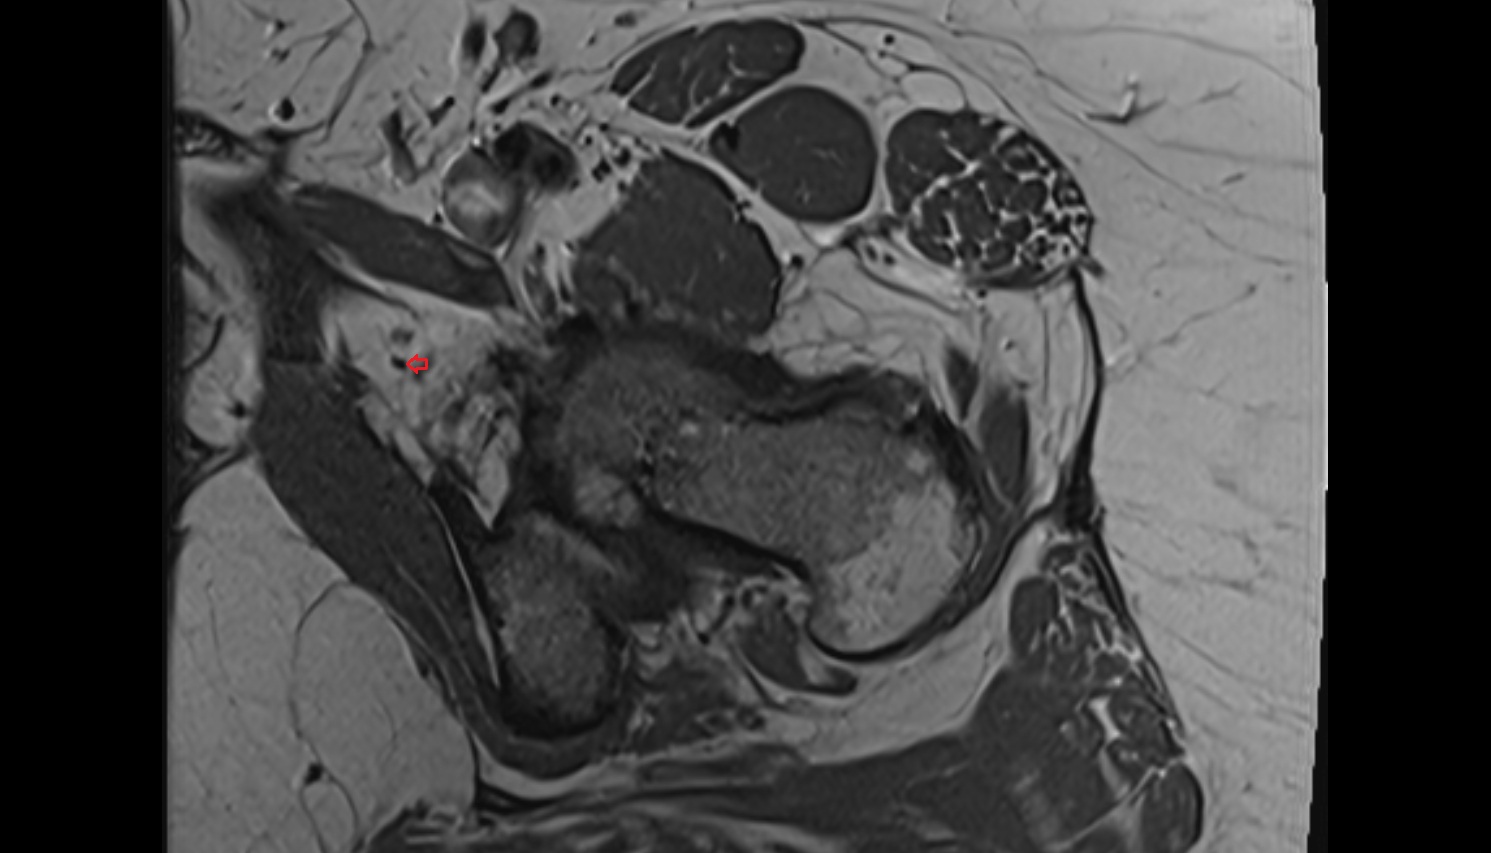

- Heart

- Left ventricle

- Right atrium

- Left atrium

- Right ventricle

- Interventricular Septum

- Left atrioventricular valve (mitral or bicuspid valve)

- Right atrioventricular valve (tricuspid valve)

- Myocardium

- Endocardium

- Epicardium